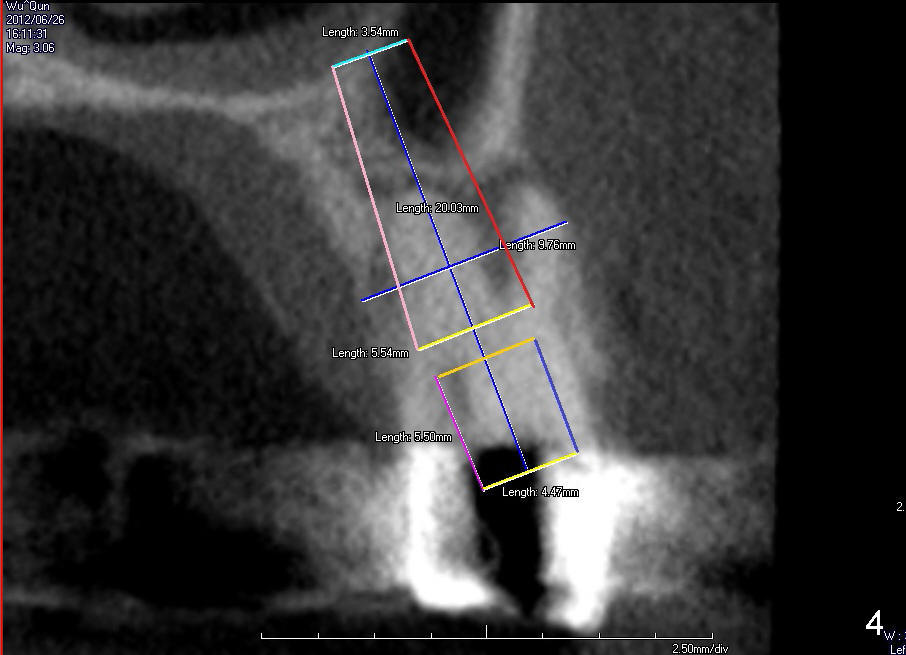

The tooth #13 has broken down to residual root now.  CBCT sagittal (Fig.1,3) and coronal (Fig.2,4) sections show designs of T (4.5x17 mm Fig.1,2) and D2 (Fig.3,4) implants.  Which is better?  It appears that sinus lift with bone graft is expected.